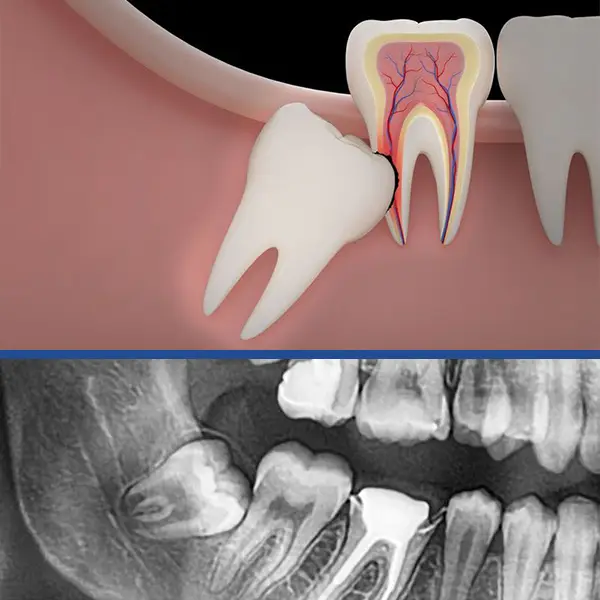

Wisdom teeth are also called third molars , and are said to be “impacted “ if they are prevented in any way, from coming into the mouth properly. These teeth normally erupt into the mouth between 17 and 25 years of age. There is sometimes a delay of eruption and occasionally they never erupt. Frequently this is a sign that the wisdom teeth are impacted.

There are many reasons for having impacted wisdom teeth removed even if they aren’t bothering you now! Most of these are discussed below;

- Orthodontic problems: Basically the pressure from impacted third molars has been blamed on teeth becoming crooked.

- Periodontal problems: A jammed wisdom tooth can cause food imapaction in the gum leading to a “pocket“ around the second molar hence loosening it.